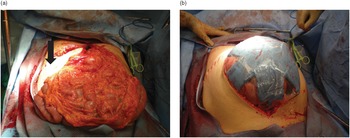

Atlas of Surgical Techniques in Trauma